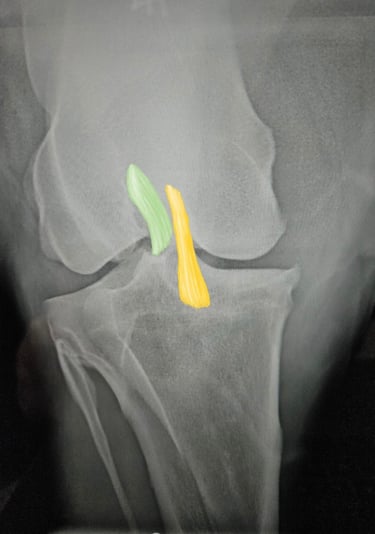

DIAGNOSTICO POR IMAGENES: ECOGRAFIA Y RADIOGRAFIA